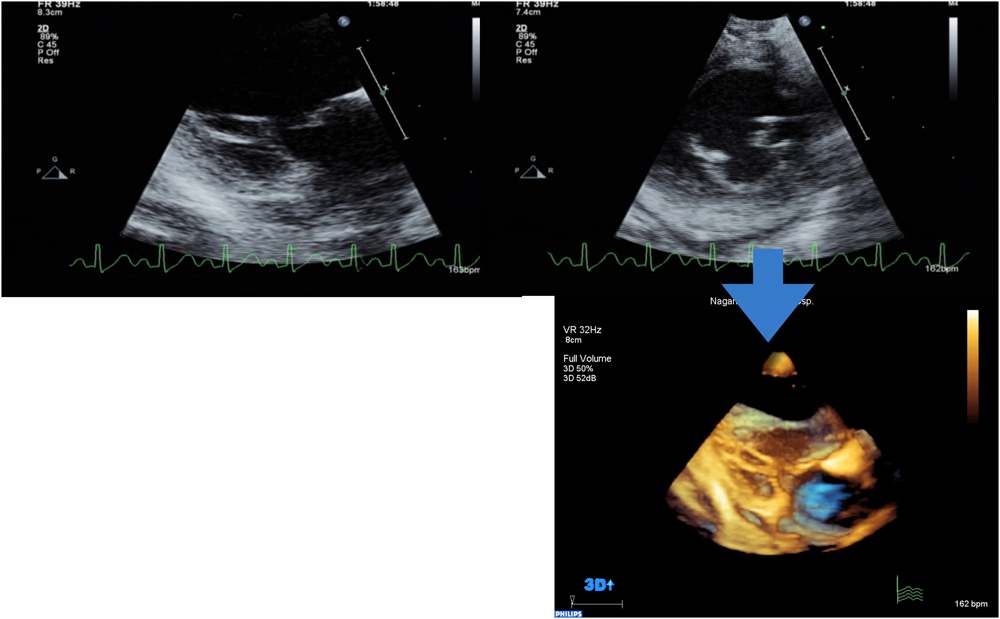

房室弁ではさらに画像収集方法に工夫が必要である.図3は,乳児の先天性僧帽弁閉鎖不全の症例である.やや心尖部からとった傍胸骨長軸断面の2D画像でよく僧帽弁が描出されているwindowを確認する.小児の房室弁は弁葉が薄いため,クロッピングの際にgainを下げてノイズリダクションすると3D画像ではさらに弁葉の輝度が低下して弁葉の画像がとんでしまいまるで孔があいているように見えてしまう.したがって弁葉の輝度が最もはっきり見えるwindowを見つけることが必要である.また,心尖四腔断面像を基に3Dを収集すると房室弁からプローベが目標物から遠くなるので,避けた方がよい.経胸壁ではこのやや心尖よりからのwindowでの収集を奨める.このwindowのままプローベを90度回転し,再度X-planeやbiplane modeで表示される長軸断面で弁葉の輝度を確認して短軸像を基に3D volume dataを収集する.するとクロッピングしたときにマルチスライスによるスティッチが入らない.

図3 先天性僧帽弁閉鎖不全におけるecho window

左室長軸断面をやや心尖部よりからのwindowより2D画像を撮像し,そこを基本のwindowとしてfull volume dataを収集する.